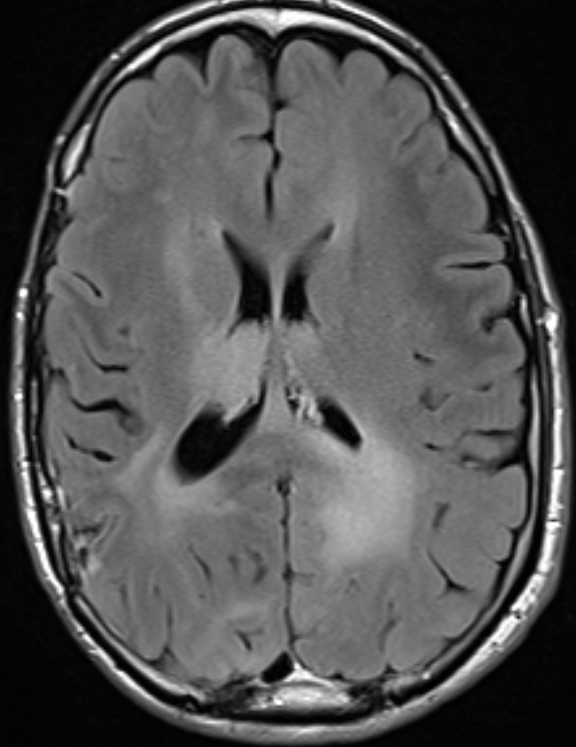

Here is a case example from a patient I treated a while back

Grade 2 glioma on the right side, treated with resection and adjuvant RT

1748327178095.png